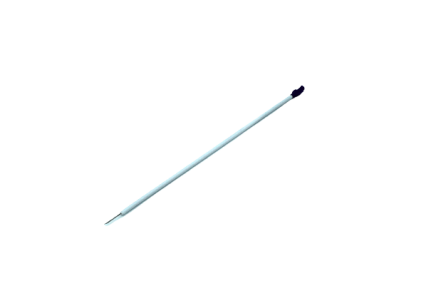

Ultimate Veress Needles

Veress Needles

Aspiration Needle